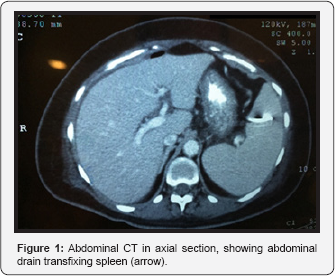

The patient remained hospitalized receiving a conservatory treatment associated with hyperbaric oxygen therapy, showing satisfactory and continuous improvement of her condition and a progressive reduction of the abdominal drain debit, with an improvement of the drained secretion aspect; regardless of showing mild pain on the left upper quadrant and occasional fever (she was receiving antibiotic therapy). She occasionally displayed sudden secretion elimination with a dark maroon color in the abdominal drain of the collecting bag along with a mild and transitory hypotension. The patient was, therefore, submitted to a new total abdomen CT scan (Figure 1 & 2), with the observation of an abdominal drain where its extremities were in the inferior spleen region, not to mention peripheral splenic hypotransparent areas; which may be related to infarct regions. Because of this, the patient was diagnosed with transfixing lesion of the spleen by the tubular drain.